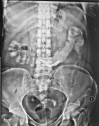

Transmigration and spontaneous passage of a gossypiboma documented on contrast study

Gossypiboma or textiloma is a rare but very unfortunate complication of surgery. It refers to a retained foreign body usually forgotten within the abdominal cavity at the end of an operation. It may be a surgical sponge, gauze pad or other form of textile. We present the case of a middle aged lady who following cholecystectomy had a forgotten gauze which underwent transmural migration and was later expelled via the rectum demonstrated by radiological studies.